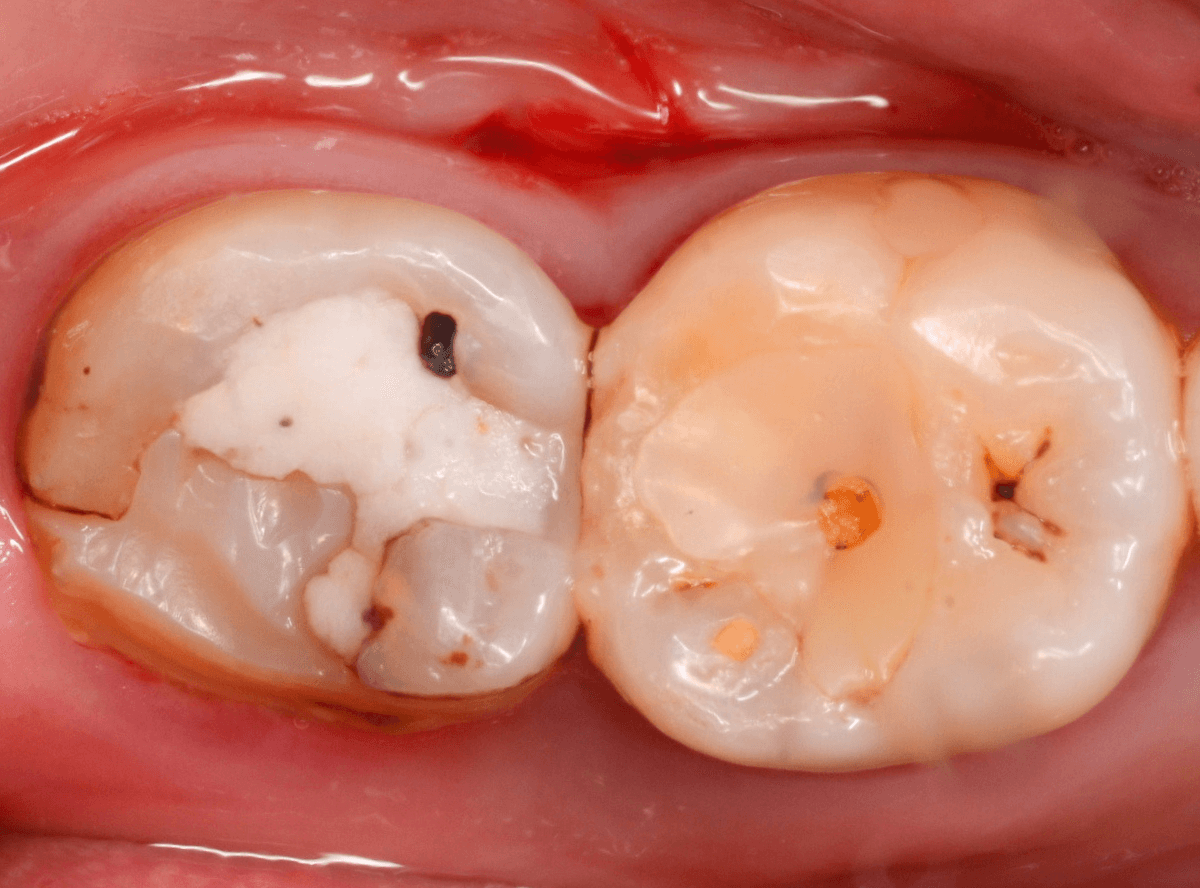

Case.14 CR(コンポジット・レジン)の下の深い虫歯

奥歯で咬んだ時に、痛みを感じるという訴えで来院された患者さんです。

パッと見は特に問題なさそうな状態ですが、大きなレジン治療がしてあり、レジンの奥もボヤっと黒っぽく見えてアヤシイ感じです。

麻酔をして、治療を開始します。

レジンを外すと、中から出血してきました。

これは、歯のスキマに歯肉が入り込んでしまったために起こってしまったものです。

おそらく、随分前から虫歯が進行していたと思われます。